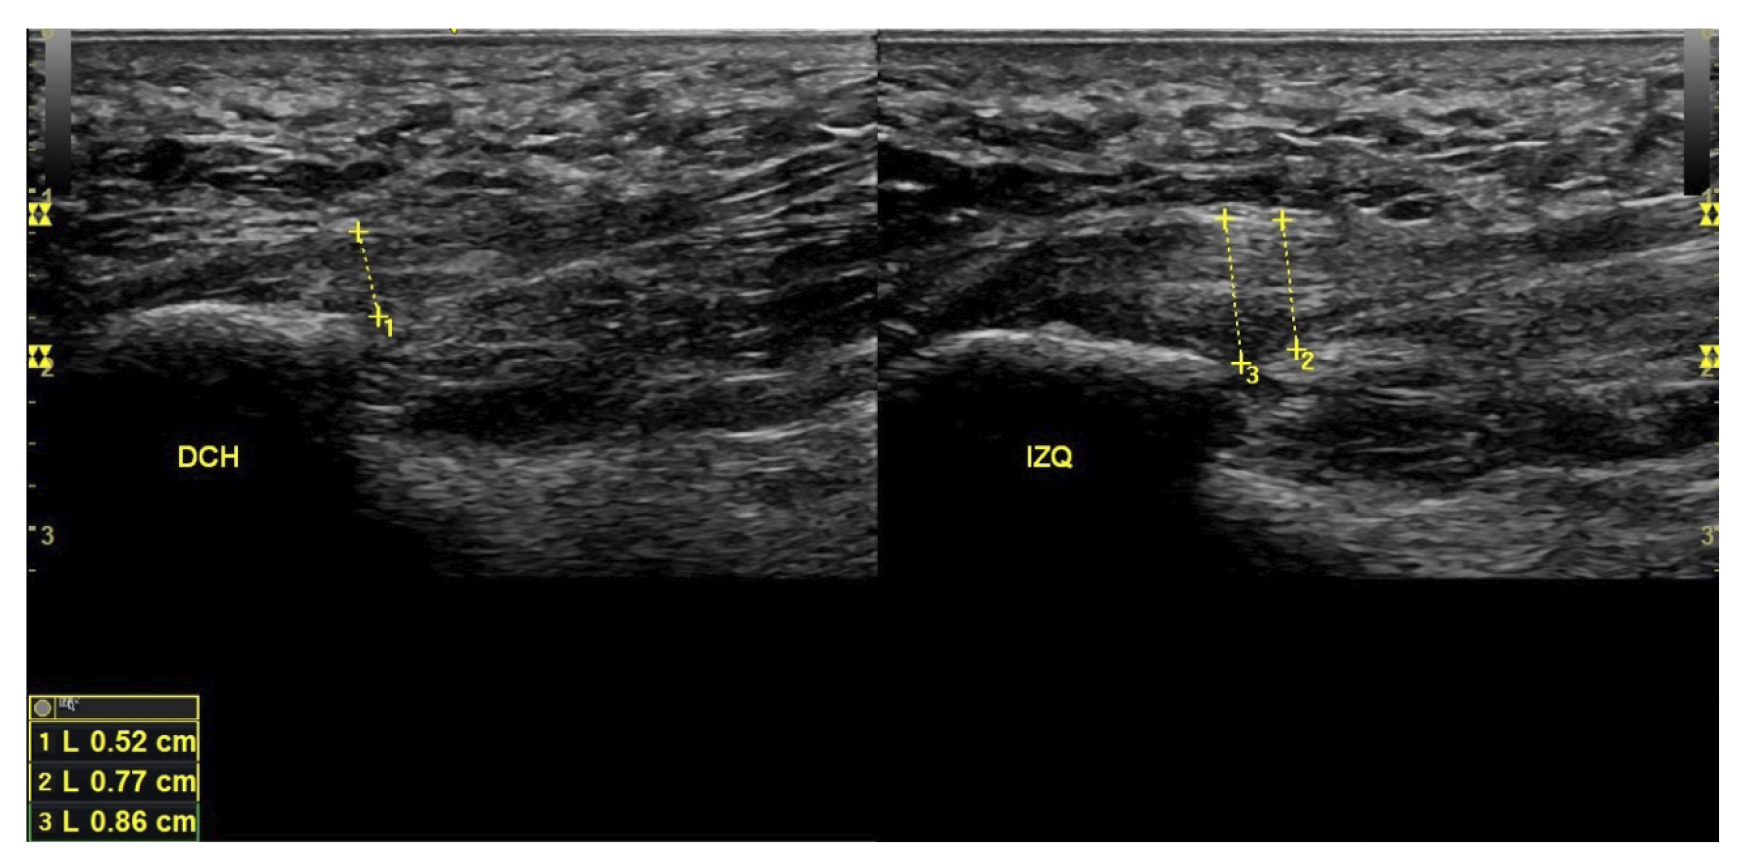

A todos los pacientes se les realizó una evaluación clínica y una evaluación ecográfica. La evaluación clínica se basó en una escala analógica visual (EVA) (13) (0-10) y el índice de función del pie (FFI) (14,15), que evalúa la función en una escala de 0 a 100. También se clasificó a los sujetos como sedentarios, activos o deportistas en función a su actividad física diaria, así como si era la primera vez que aparecía la enfermedad, era una recidiva o era crónica(16). También se evaluó el sexo, el peso y la talla, la presencia de vascularización en la fascia plantar visualizada con ecografía en el momento de la evaluación inicial y la forma biconvexa(17) o aplanada de la fascia plantar (Figura 1).

El diagnóstico se estableció en base a los síntomas y se confirmó mediante ecografía con equipo de alta resolución (Alpinion Ecube 9, ALPINION MEDICAL SYSTEMS Co., Ltd., República de Korea) con transductor lineal de 6 a 12 MHz (Figuras 2 y 3).

Figura 3. Área de medición del grosor de la fascia plantar. La línea punteada corresponde con la medición del grosor.